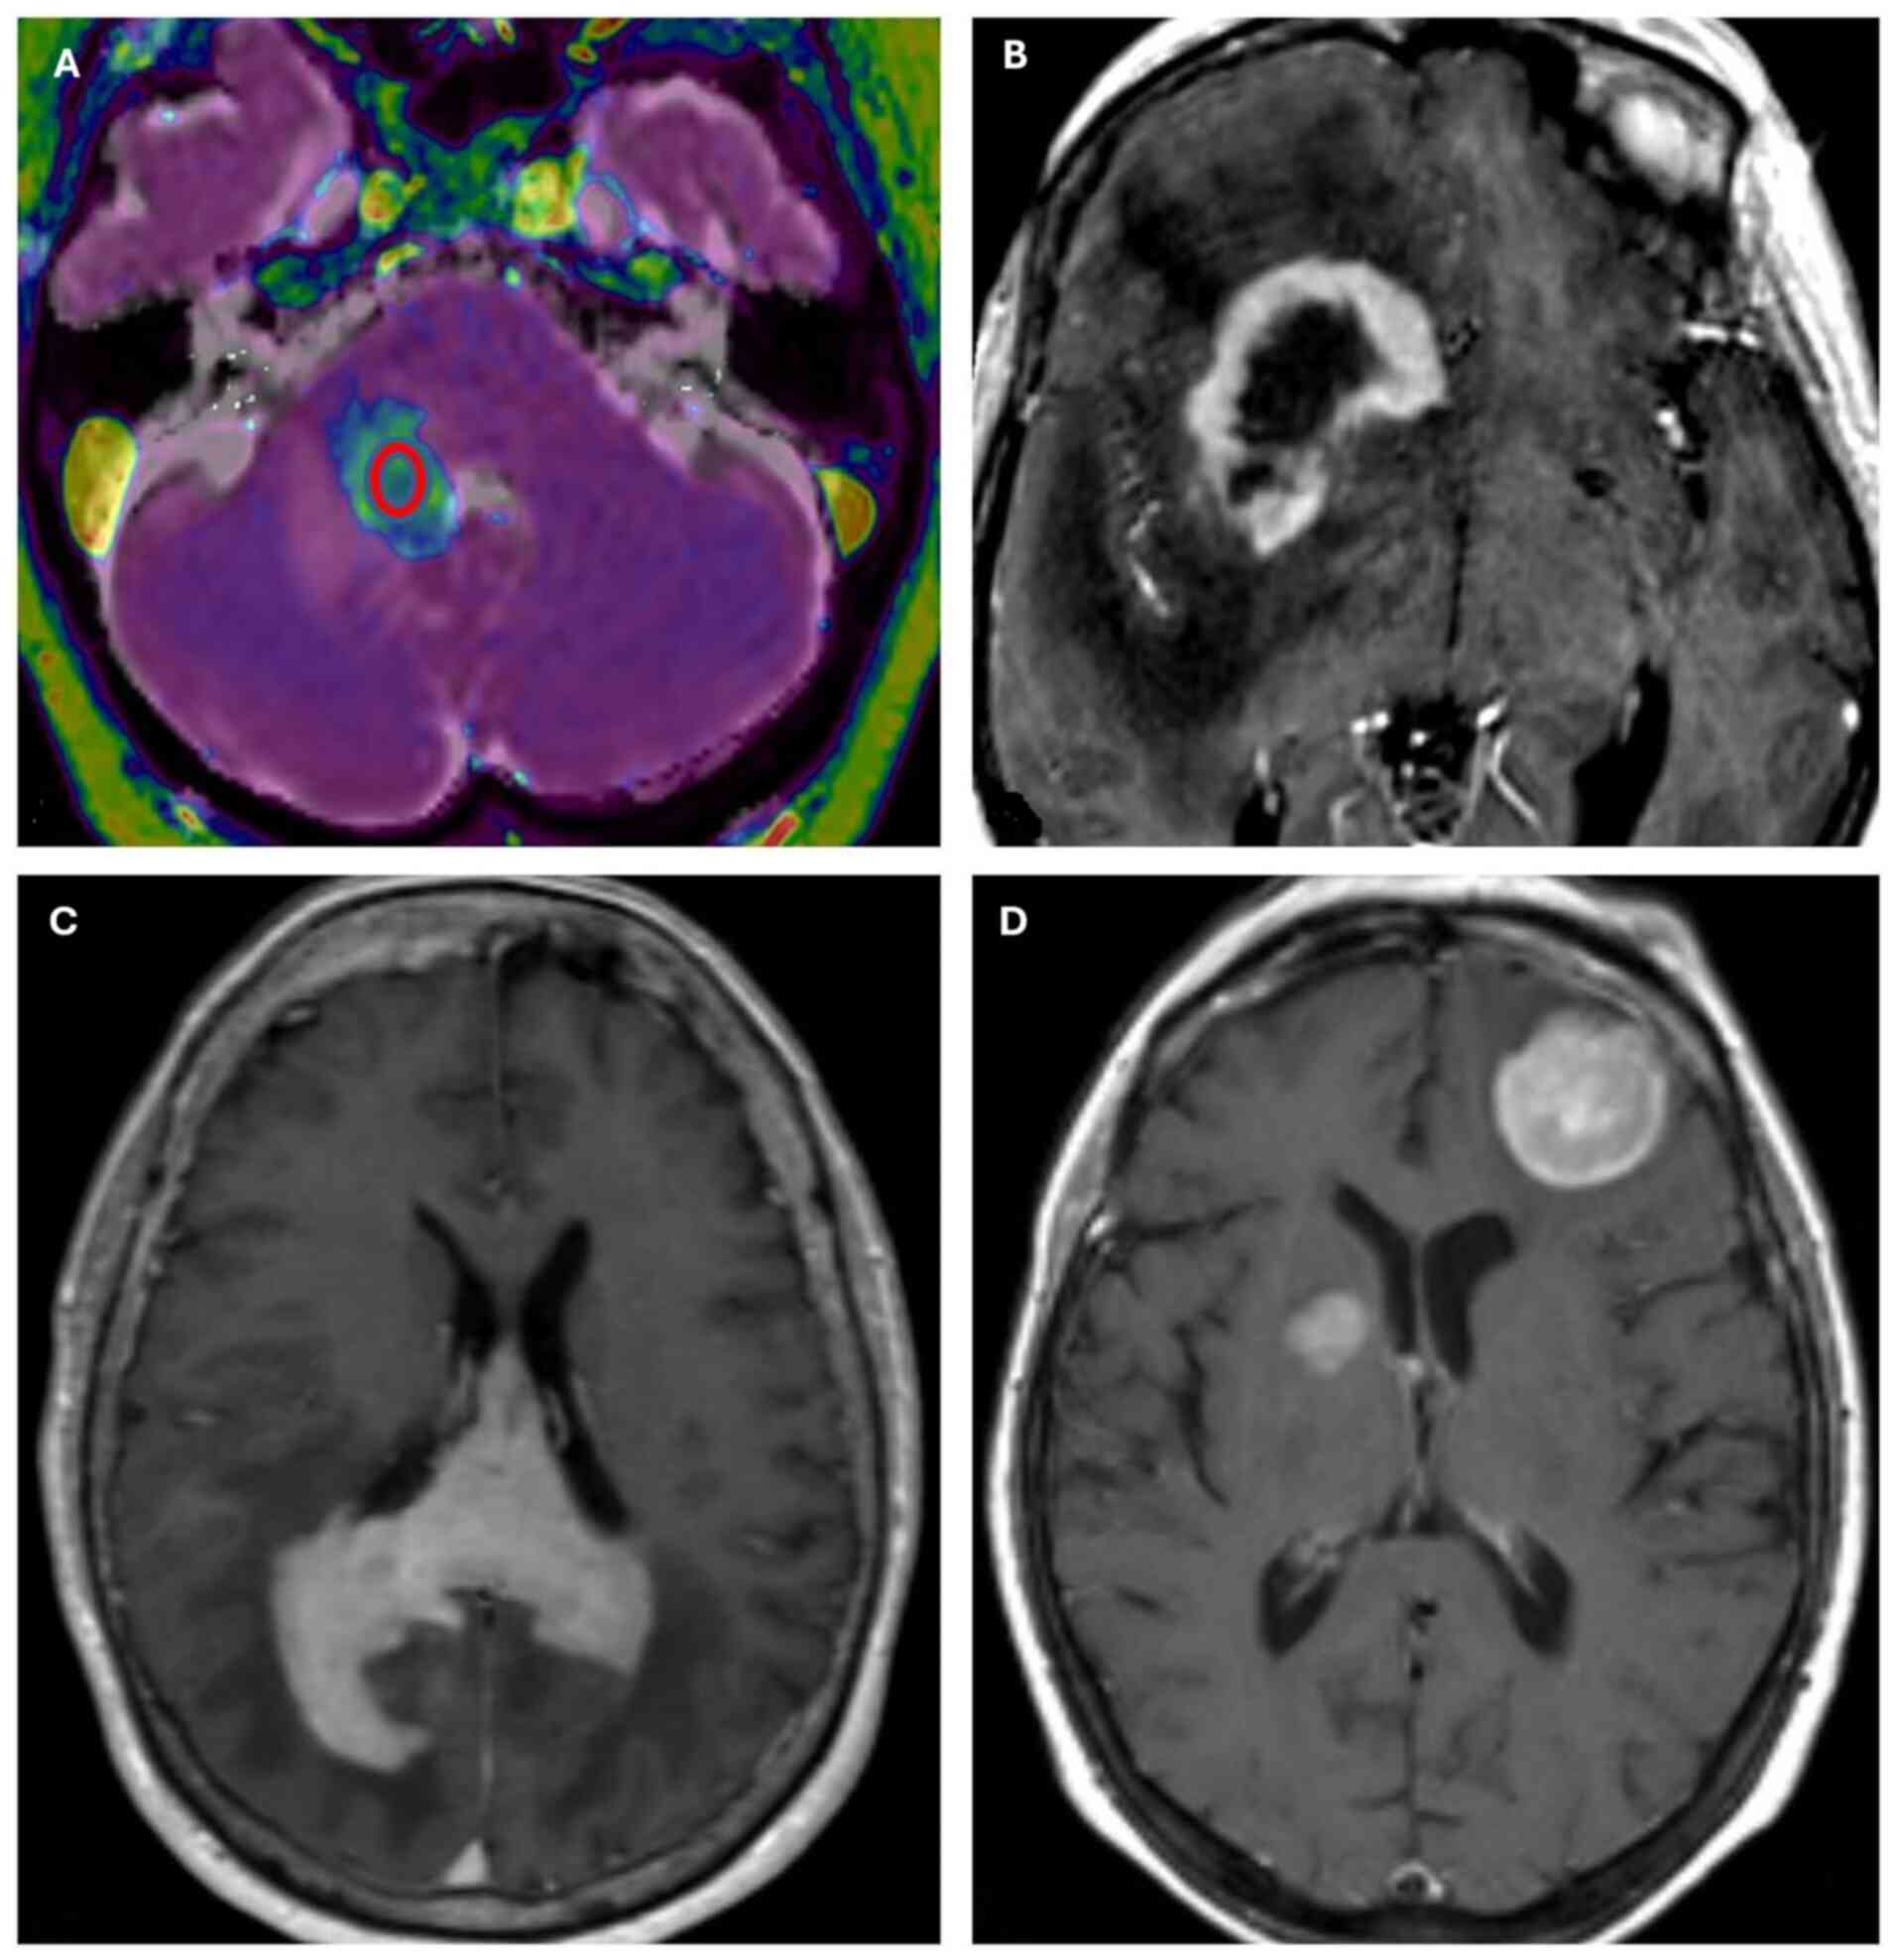

Of the total of 23 patients, 20 (87%) were ≥60, and 3 (13%) were <60, with a median age of 66 and a mean age of 65.7; 8 patients (35%) were male and 15 (65%) female. Supratentorial disease was documented in 18 cases (78%), and infratentorial disease in 5 cases (22%) (Table I). Regarding neuroradiological features, MRI images showed homogeneous enhancement in 21 out of 23 cases and ring enhancement in 2 out of 23 patients, which can be considered an expression of central tumor necrosis. Fourteen out of 18 supratentorial cases revealed invasion of the corpus callosum and other median line structures, while infratentorial cases did not exhibit this feature. Multifocal disease was indicated in 14 out of 23 cases and unifocal disease in 9 out of 23 cases (Fig. 4). The mean ADC value was 0.53×10−3 mm2/s, with a standard deviation of 0.18×10−3 mm2/s. The mean enhancement value was 613.75, with a standard deviation of 264.66. Two subgroups were identified based on age: those ≥60 included 4 GCB cases (20%) and 16 Non-GCB cases (80%), with a mean Ki-67 value >80%; the second subgroup included 2 GCB cases and 1 Non-GCB case, with a mean Ki-67 value of 57%. The mean Ki-67 value was 82.5% in male patients and 71% in female patients.

MRI features of primitive diffuse

large B-cell lymphoma. (A) T1 magnetization prepared rapid gradient

echo post-gadolinium administration/ADC co-registration. A

region-of-interest (red circle) was drawn in the ADC map at the

center of a right cerebellar lesion. (B) Ring enhancement

indicative of central necrosis (post-contrast T1-weighted MRI). (C)

Corpus callosum infiltration (post-contrast T1-weighted MRI). (D)

Multifocal disease (post-contrast T1-weighted MRI). ADC, apparent

diffusion coefficient.

Figure 4.

MRI features of primitive diffuse large B-cell lymphoma. (A) T1 magnetization prepared rapid gradient echo post-gadolinium administration/ADC co-registration. A region-of-interest (red circle) was drawn in the ADC map at the center of a right cerebellar lesion. (B) Ring enhancement indicative of central necrosis (post-contrast T1-weighted MRI). (C) Corpus callosum infiltration (post-contrast T1-weighted MRI). (D) Multifocal disease (post-contrast T1-weighted MRI). ADC, apparent diffusion coefficient.